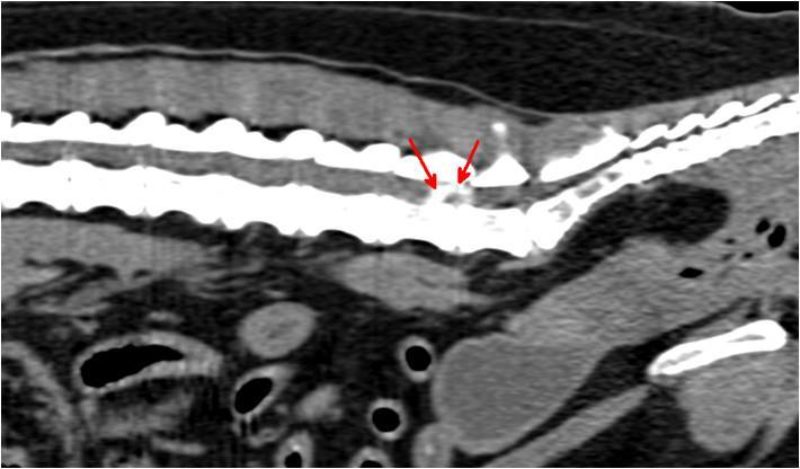

Die vor der Narkose durchgeführte Blutuntersuchung ergab keine Abweichungen von den Normalwerten. Die Röntgenbilder der Knie- und Hüftgelenke waren unauffällig. Bei der seitlichen Aufnahme der Lendenwirbelsäule fiel ein verengter und unruhiger Zwischenwirbelspalt zwischen dem 6. und 7. Lendenwirbel auf (Bild 1). Es wurde der Verdacht auf eine Bandscheibenerkrankung in diesem Bereich geäußert und den Besitzern eine weitere Abklärung mittels Computertomographie empfohlen. In der computertomographischen Untersuchung der Wirbelsäule konnte zwischen dem 6. und 7. Lendenwirbel in den knöchernen Wirbelkanal sowie in das linke Nervenaustrittsloch vorgefallenes Bandscheibenmaterial nachgewiesen werden (Bild 2 und 3). Dieses verursachte eine Kompression des Nervengewebes. Dieser Druck des vorgefallenen Bandscheibenmaterials auf das Nervengewebe war ursächlich für die hochgradige Schmerzhaftigkeit.